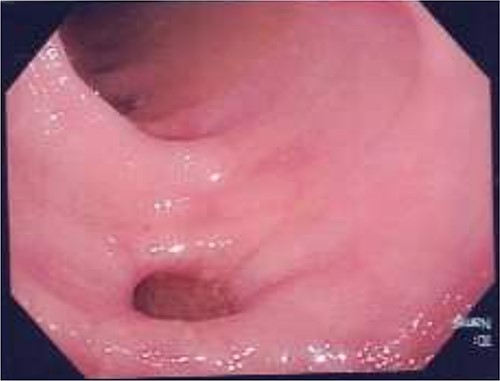

The patient was admitted under the surgical team and commenced on intravenous antibiotics for 2 days, and then was discharged. Colonoscopy was then performed 2 weeks following discharge, revealing sigmoid diverticulosis, no polyps and no evidence of complicated diverticulitis, as demonstrated in Fig. 2.

Colonoscopy following first hospital admission, demonstrating evidence of sigmoid diverticular disease, with no evidence of fistula formation.